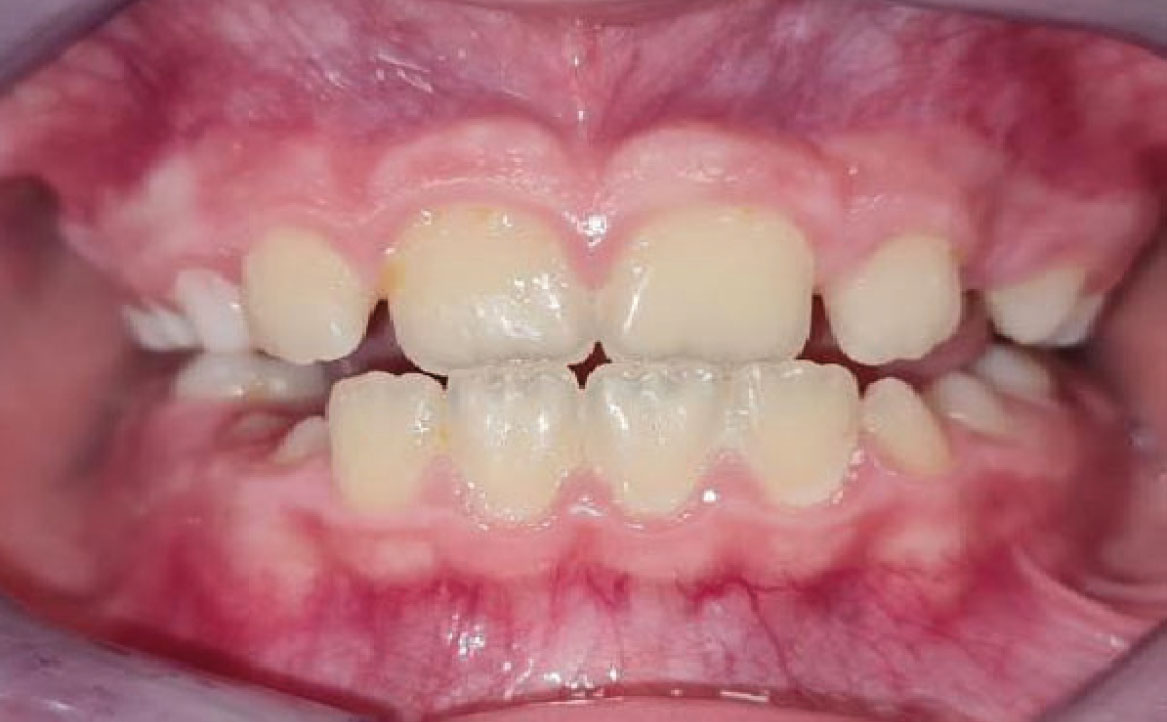

Fig. 4A Foto intraorale in massima intercuspidazione.

A livello intraorale sul piano sagittale è osservabile I classe molare destra e sinistra e classe canina non valutabile per mancanza degli elementi dentari durante la fase di permuta.

L’overjet e l’overbite sono entrambi ridotti in massima intercuspidazione. Trasversalmente il mascellare superiore è contratto (fig. 4-7).